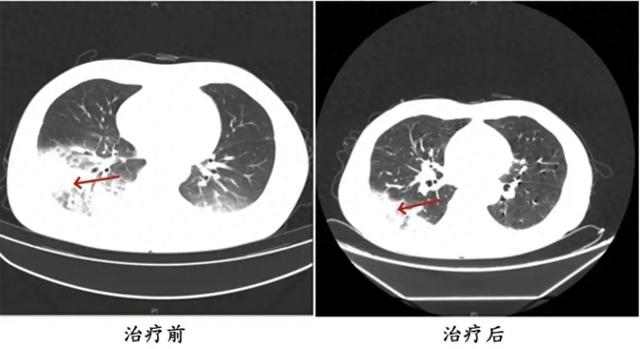

医生判断患者有可能感染了军团菌 , 建议患者完善纤支镜检查 , 留取肺泡灌洗液标本查找病原体 。 最终 , 患者肺泡灌洗液NGS(Next-Generation Sequencing , 下一代测序)检测结果显示:嗜肺军团菌 , 明确诊断为军团菌肺炎 。 医生马上调整治疗方案 , 改用可覆盖嗜肺军团菌的一线用药抗感染 , 患者体温逐渐下降 , 次日体温恢复正常 , 经过后续治疗康复出院 。

周先生治疗前后的肺部CT影像